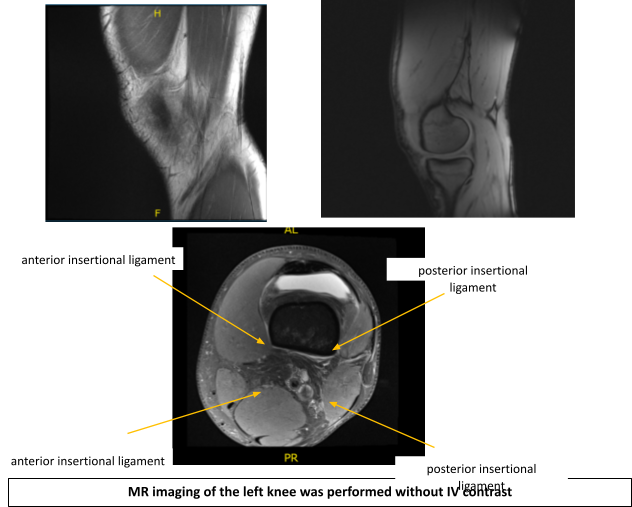

An MRI was performed. There is a complex tear of the lateral meniscus with displacement of the majority of the posterior horn and body-posterior junction displaced anteromedially, immediately posterior to the anterior horn.

There is intra-meniscal cyst formation within the displaced meniscus as well as within the native anterior horn with a cluster of parameniscal cyst seen anteriorly measuring up to 1.2 x 1.4 x 1.5 cm (craniocaudal x anteroposterior x transverse dimension). There is full-thickness cartilage loss overlying the central weight bearing aspect of the lateral femoral condyle spanning approximately 1.4 x 0.5 cm with a nondisplaced delamination flap medially.